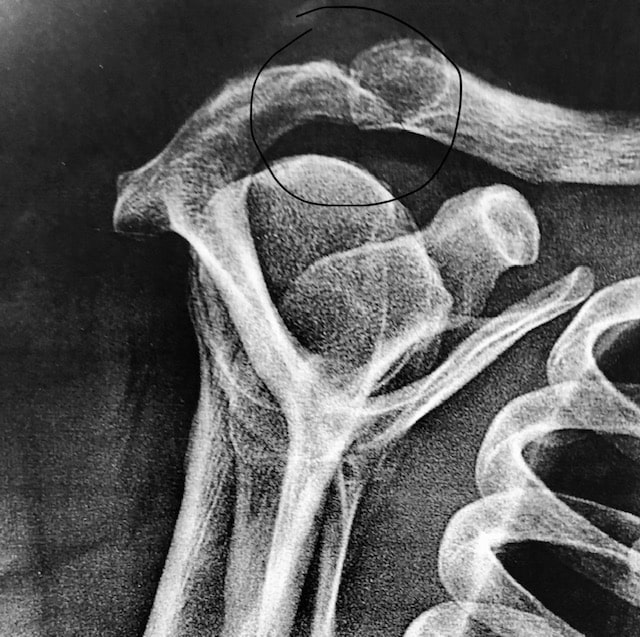

Fracture de la scapula (omoplate)

L’omoplate, os fin et plat, soutient le membre supérieur par l’articulation gléno humérale. Elle repose sur le grill costal et glisse dessus par un plan de glissement.

Les fractures de la scapula, souvent liées à un accident de sport ou de la voie publique, nécessitent le plus souvent un traitement orthopédique par le port d’une écharpe coude au corps (Dujarrier) durant 3 semaines avec un début de rééducation précoce. La richesse des muscles s’insérant sur l’omoplate permet un cal osseux (consolidation de la fracture) précoce.

De rares indications chirurgicales existent, notamment en cas de fracture de la glène déplacée car il existe alors un risque de dysfonctionnement de l’articulation gléno humérale, puis d’arthrose. Dans ce cas, la chirurgie se fait généralement par une voie postérieure, à l’aide de plaques vissées.